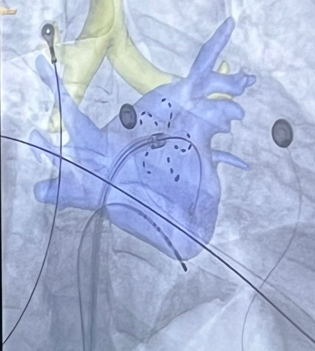

👨⚕️ El Dr. Marco Tomasino, cardiòleg de #VallHebron, ens mostra com tractem les arrítmies amb camps elèctrics polsats. Només destruïm molt selectivament el teixit cardíac que causa l'arrítmia.

✅ L'ablació cardíaca és una tècnica per tractar trastorns de la freqüència cardíaca.